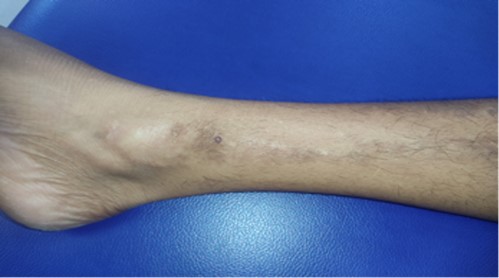

We report a 26-year-old female with a history of atopy, who presented with severe itching and scratching over bilateral lower legs and forearms for past six months. Local examination revealed rippled macules and papules coalescing into plaques and patches on bilateral lower legs and forearms (Fig-1). A biopsy was performed on the right medial malleolus of the right leg.

Figure 1: Local examination showing macules and papules coalescing into plaques and patches on leg.